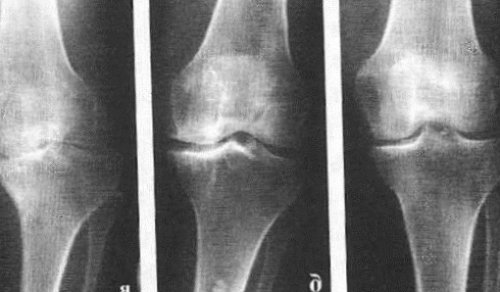

Независимо от причины возникновения выделяют три стадии заболевания гонартроза, или деформирующего артроза коленного сустава.

Гонартроз, II стадия

На второй стадии хрящевая прослойка резко истончается, а местами и вовсе отсутствует. Появляются остеофиты по краям суставных поверхностей. Изменяются качественные и количественные характеристики синовиальной жидкости сустава — она становится гуще, более вязкой, что приводит к ухудшению питающих и смазывающих свойств. Боли более продолжительные и интенсивные, часто при движении появляется хруст. Отмечается незначительное или умеренное ограничение движений и небольшая деформация сустава. Прием анальгетиков помогает снять болевой синдром.

Гонартроз, III стадия

Отсутствие хряща на большинстве поражённых участков, выраженный склероз (уплотнение) кости, множество остеофитов и резкое сужение или отсутствие суставной щели. Боли практически постоянные, походка нарушена. Подвижность резко ограничена, заметна деформация сустава. Препараты НПВС, физиопроцедуры и другие стандартные методы лечения артроза коленного сустава неэффективны.

В подавляющем большинстве случаев достаточно осмотра и рентгенограммы коленного сустава в двух проекциях (прямой и боковой). Клинические данные и снимки позволяют определить стадию заболевания.